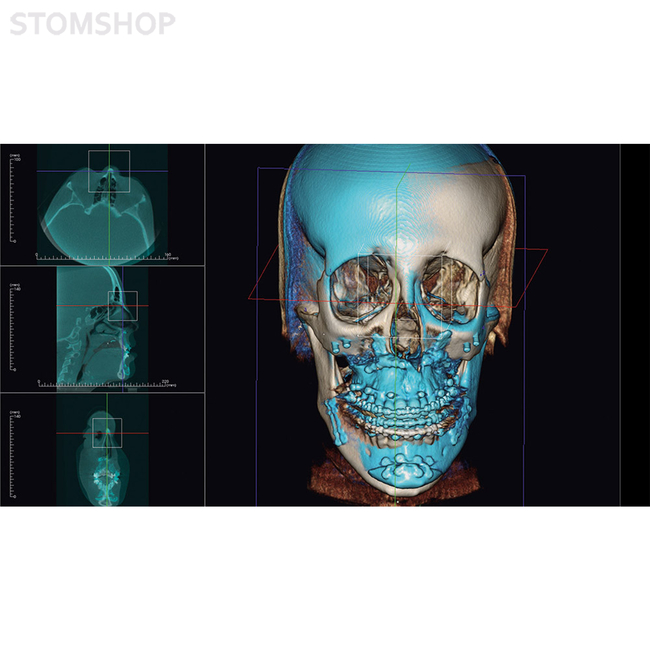

Ортодонтия: план лечения с повышенной точностью

Челюстно-лицевая хирургия и MJF (ротовая, лицевая, челюстная хирургия): определение характера хирургического вмешательства

Необходимое вам программное обеспечение будет установлено в OP 3-D Vision во время эксплуатационного запуска. В перечне предустановленного ПО есть поддержка трехмерной рентгенографии, хирургические шаблоны для планирования имплантатов и имплантационной хирургии, другие варианты применения по выбору.

Ваша рентгенографическая система KaVo OP 3-D Vision готова для будущей эксплуатации: вы можете заказать DTX Studio, новую программную платформу, разработанную в виде целостной системы организации технологических процессов. DTX Studio постоянно оптимизируется и охватывает все области современной стоматологии и дентальной технологии в будущем. DTX Studio совместимо с операционными системами Mac и Windows. Оно будет объединять как уже существующие, так и проектируемые устройства многочисленных брендов, а также современные возможности программного обеспечения в объединенный рабочий процесс.